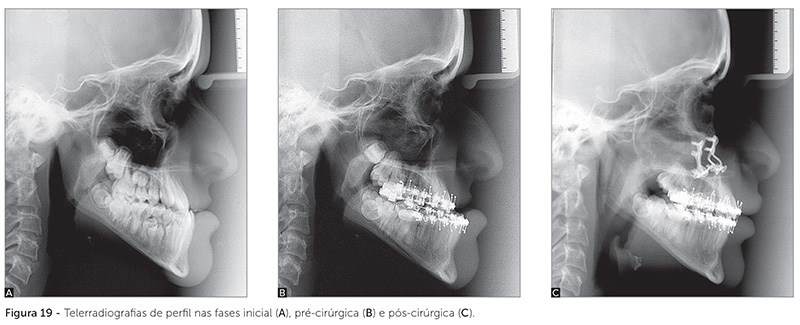

No tratamento de pacientes Classe III, temos bons resultados nas faixas etárias de 7 a 10 anos, quando a má oclusão é leve ou moderada; na faixa etária de 17 a 19 anos, quando temos o consagrado tratamento ortodôntico-cirúrgico, ou nos casos de menores discrepâncias maxilomandibulares, temos a opção da camuflagem ortodôntica6. Na vida clínica, sempre senti um vácuo no atendimento de pacientes Classe III, com grande deformidade dentária e facial, na faixa etária de 12 a 14 anos: tarde para uma abordagem interceptativa, cedo para a cirurgia. A hipótese de aguardar o final do crescimento para se iniciar o tratamento ortodôntico-cirúrgico por vezes se mostra extremamente difícil para o paciente portador de deformidade facial severa. É difícil explicar ao paciente e responsáveis que o tratamento só acontecerá depois de 4 ou 5 anos. Portanto, o tratamento ortodôntico-cirúrgico pode ser realizado durante a fase de crescimento ativo, em casos de grandes desarmonias esqueletais, quando o paciente estiver estética, psicossocial e/ou funcionalmente comprometido7 — como pode ser visto no caso apresentado nas Figuras 16 a 20. Para que essa terapia possa ser indicada, devem ser observados critérios ortodônticos como pouca discrepância intra-arcada e possibilidade de preparo pré-cirúrgico sem grandes recolocações dentárias. Um segundo tratamento ortodôntico-cirúrgico provavelmente se fará necessário após o término do crescimento. Esse tratamento não deve ser considerado tratamento de rotina, mas sim uma possibilidade terapêutica para casos criteriosamente selecionados7,8.

A idade mínima para indicação de cirurgia ortognática em fase de crescimento estará diretamente relacionada ao grau de desenvolvimento da dentição. Portanto, em todos os tipos de deformidades faciais severas em que a abordagem da cirurgia precoce for considerada — seja na hiperplasia ou hipoplasia mandibular, na hipoplasia maxilar ou na hiperplasia maxilar vertical —, o estágio do desenvolvimento dentário será determinante para o procedimento cirúrgico. O grau de desenvolvimento dos caninos superiores é importante para avaliarmos a viabilidade da cirurgia maxilar sem dano à estrutura dentária. É recomendável fazer a cirurgia de avanço mandibular após a erupção dos segundos molares inferiores; o ideal seria ter todos os dentes permanentes já irrompidos, exceto os terceiros molares. Algumas vezes, temos que esperar um pouco para realizar a cirurgia, para que ocorra maior desenvolvimento dentário. Um exemplo de paciente tratado aos 12 anos de idade pode ser visto nas Figuras 21 a 25, quando o desenvolvimento dentário já permitia as manobras cirúrgicas necessárias. O que não pode acontecer, seja por essa ou por outra razão, é propormos a cirurgia a um paciente Classe III em seus 15 ou 16 anos de idade. Essa não me parece uma abordagem sensata. Seria correto aguardar até os 18 anos de idade e realizar o consagrado tratamento ortodôntico-cirúrgico da Classe III.